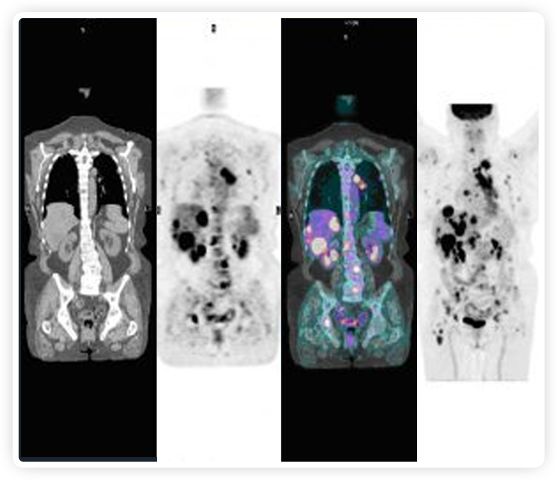

PET+放療共同治療

RefleXion將PET成像與立體定向放射治療相結(jié)合。在注射示蹤劑后,RefleXion的技術基于示蹤劑信號實時地在一個或多個目標上引導治療性X射線。使用這種專有方法,RefleXion的平臺有可能比現(xiàn)有系統(tǒng)向癌癥病變提供更高劑量的輻射,并改善周圍健康組織的保護。

為了避免PET長圖像采集時間,RefleXion開發(fā)了一項專利技術使用重合的PET光子對來指導放射治療束,因為實時檢測發(fā)射的光子,為生物指導提供了一種時間有效的方法。